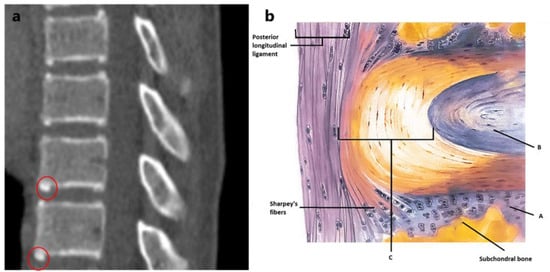

2.2. CT-Scan Analysis

- Phase 0: Ring not detectable.

- Phase 1: Ring detectable.

- Phase 2: Fusion not completed.

- Phase 3: Fusion completed.